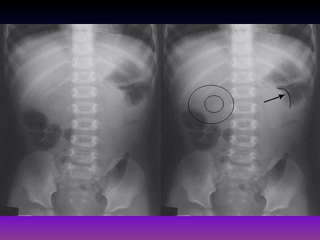

Cutis Laxa